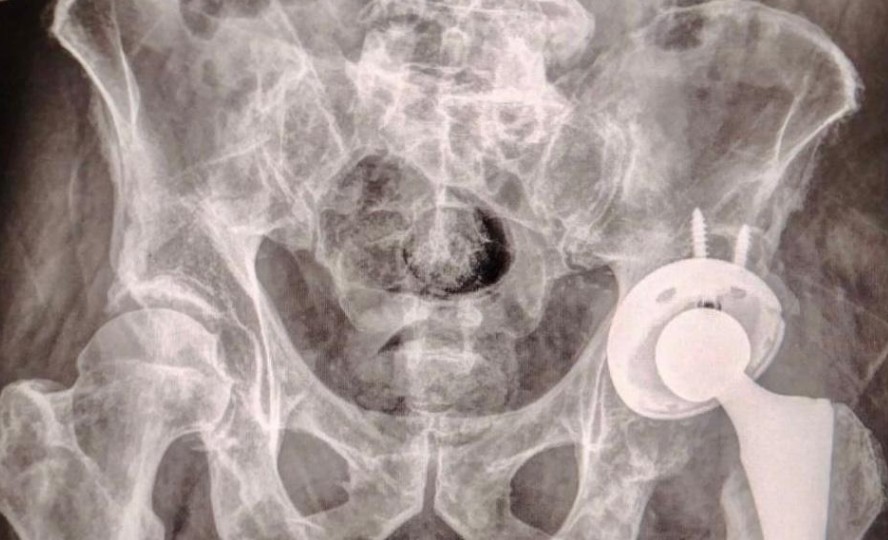

ISSSTEP coloca con éxito la primera prótesis de cadera sin costo

En un hecho histórico para la salud en Puebla, el Instituto de Seguridad y Servicios Sociales de los Trabajadores al Servicio de los Poderes del Estado de Puebla (ISSSTEP) realizó con éxito la primera cirugía de colocación de prótesis de cadera sin costo para el paciente.

Este logro forma parte del Programa de Cirugía Articular impulsado por el Hospital de Especialidades, y representa un hito en la atención de enfermedades osteoarticulares, al priorizar la gratuitad, la tecnología médica y la bioética social como ejes del servicio.

La cirugía fue realizada por un equipo multidisciplinario altamente capacitado, bajo estrictos protocolos de seguridad y criterios clínicos de selección. Esta intervención está dirigida a pacientes con desgaste articular severo, cuyas condiciones afectan su calidad de vida y movilidad.

El programa se enfoca en ofrecer tratamientos quirúrgicos de alta especialidad, garantizando el cuidado del paciente desde el preoperatorio hasta el seguimiento posquirúrgico, y empleando tecnología médica avanzada junto al fortalecimiento de las capacidades humanas del personal.